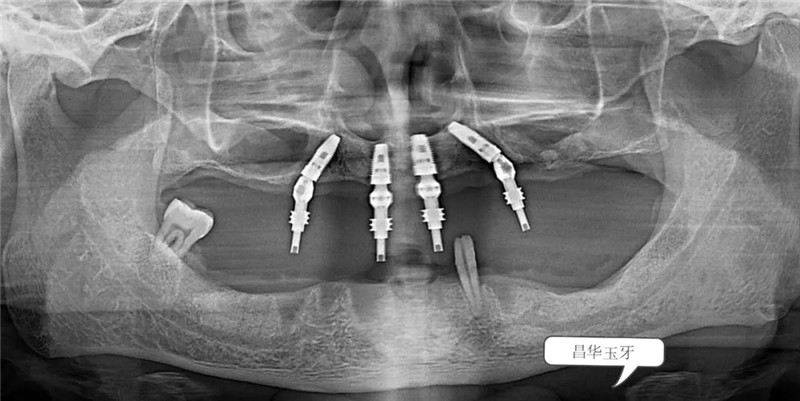

无论是直接的口腔检查还是从全景片上来看,这位患者全口牙列所剩无几,患者自述过程中亦可听出患者是饱受无牙之苦。也确实,从面容到进食再到发音均受牙齿缺失的影响。(如下图)

根据患者的口内情况,结合X光片,为患者设计全口牙种植All-on-4。并在一系列的术前准备之后,我院特邀——省口腔家白彭主任为患者植入4颗植体,手术微创、全程无痛,并在12月20日傍晚,白主任为患者装上上半口固定牙冠,患者很满意。